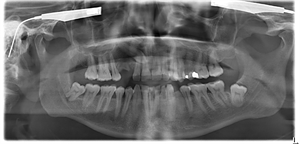

Orthopantomogram

February 28, 2015

Panorex is a diagnostic full mouth x-ray

The panoramic x-ray is a dental radiograph showing the upper and lower jaw. It is also known as OPG, panoral, panorex, orthopantomogram or a full mouth radiograph.

An orthopantomogram (OPG) is an x-ray image of the whole of your lower face and jaw which shows a two-dimensional (2-D) view of the dentition, mandible, maxilla and temporomandibular joints. Although the term sounds very complicated, it is also known simply as a panoramic x-ray, full mouth x-ray, panoral or panorex.

One of the advantages of an orthopantomogram is that there is no need to place x-ray film inside the mouth, and the dosage of radiation received by the patient is less than taking separate x-rays of the teeth. The procedure will show all of the teeth (32 of them in a fully grown adult with all four wisdom teeth) including teeth which may not have erupted. It can also display problems like:

1. Horizontal and vertical bone loss

2. Extensive tooth decay

3. Oral cysts

4. Tooth abscesses

5. Impacted teeth

6. Supernumerary (extra) teeth

7. Temporomandibular joints disorder

8. Oral cancer

9. Jaw fractures

10. Positioning of dental implants

11. Sinusitis

Orthopantomograms can be used to determine planning and treatment for impacted wisdom teeth, assess periodontal bone loss, and locate the source of dental pain, or toothache. They may also be used for assessment for the placement of dental implants if you are considering this procedure. In addition, there are a number of other possible diseases or malfunctions that will be visible to the dentist if they are present.